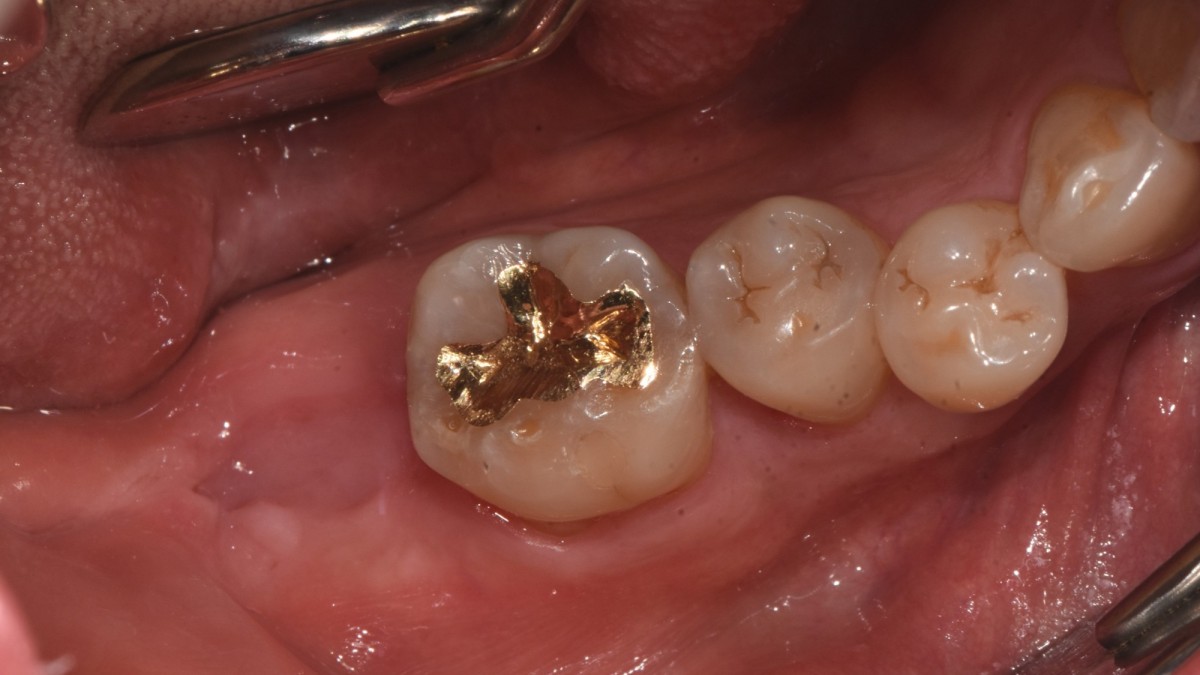

A 47-year-old male patient had a crown with an ill-fitting margin and crack-tooth syndrome in the lower 2nd molar. No systemic issue.

▲Arum Dentistry NB1 5*10